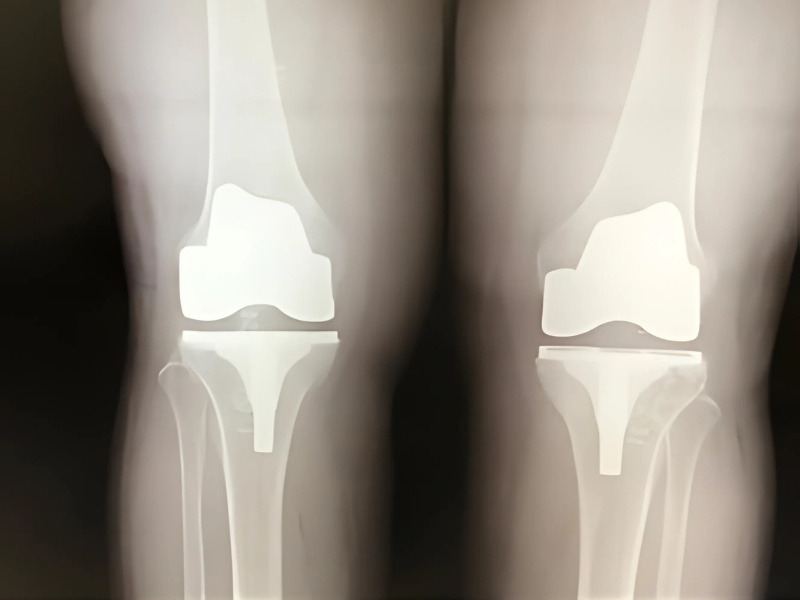

Diz protezi, travma veya ileri seviye osteoartrit (kireçlenme) gibi nedenlerle hasar görmüş veya fonksiyonunu kaybetmiş diz ekleminin yapay malzemelerle değiştirildiği ameliyattır.

Ameliyat genellikle genel veya spinal anestezi altında yapılır ve yaklaşık 2 saat sürer. İşlem sırasında hasarlı kıkırdak ve kemik dokusu çıkarılarak önceden ölçülü şekilde hazırlanan protez yerleştirilir.